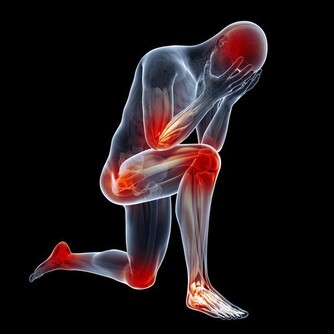

男人六個不健康的表現:

頭痛:

當出現頭痛的症狀時,你可能並不會在意,或者過一段時間就能自己的緩解,其實這小小的表現不去理睬,也會發展為大問題,尤其是在休息之後仍然不能消除,或是出現很長的時間,那麼就是你的身體向你發出了“危險”的警號,你就要高度的重視,不要聽之任之,無視其存在,以免帶來更多的危害,應當多調整自己的生活方式,放鬆身心,多注意休息。

睡眠障礙:

當男人們經常出現難以入眠或間斷多醒、早醒的症狀,就要關注自己的健康了,睡眠對於身體的功能修復十分重要,睡眠不僅僅是使人恢復體力和腦力、消除疲勞,更重要的是能使人體保持免疫能力,使自身能抵禦疾病的侵擾。缺少睡眠能使免疫能力大大降低,更容易患上疾病。男人工作繁忙壓力大是導致睡眠障礙的主要原因,經常加班熬夜,為工作應酬喝酒,為保持工作狀態而喝咖啡、濃茶等,這些行為都容易導致睡眠節律的紊亂。

肥胖:

不要認為肥胖只是營養充足的表現,男人過於肥胖是很多疾病的罪魁禍首,而如今越來越多的男人出現肥胖問題,攝取過多的熱量和脂肪,而缺少運動是很多上班族男性肥胖的主要原因,肥胖的男人更容易疲勞、腰酸背痛。也容易引起脂肪肝、糖尿病、高血脂、高血壓,還可能造成男人的心理障礙。

性功能障礙:

男人們的自尊心很強,性功能不行的話很傷面子,男人健康問題除了日常的不適表現外,還容易引起性功能的問題,當男人們清晨的自然勃起消失、性慾減退,在性生活中不能維持長時間,還有陽痿早洩功能,這都是一些不正常的生理現象,男人們要關注自己的健康了。

煩躁抑鬱:

心情不好也是我們都常有的,短暫的心情煩躁抑鬱都是正常的,但經常煩躁抑鬱,

精神上出現記憶力的減退、精神恍惚、情緒悲觀沮喪、

有時候很難的控制自己的情緒變化時,不僅要採取心理的治療,也要注意身體上的疾病了。